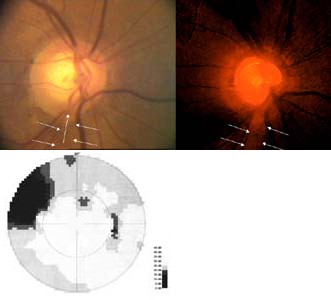

Tento terč má exkavaci protaženou vertikálně a temporálně od obou pólu jsou patrné výpadky nervových vláken. V zorném poli se projevil výpadek vycházející z horní oblasti terče, kde je i peripapilární hemorhagie, jako skotom v nasální dolní části zorného pole s ostrou hranicí v horizontále.